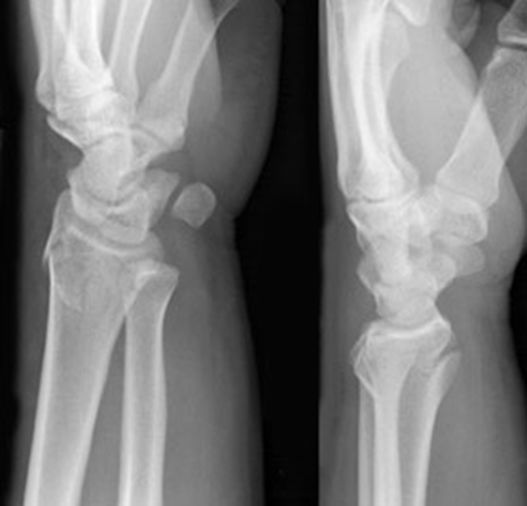

孟氏骨折

• 尺骨骨折

• 桡骨头脱位